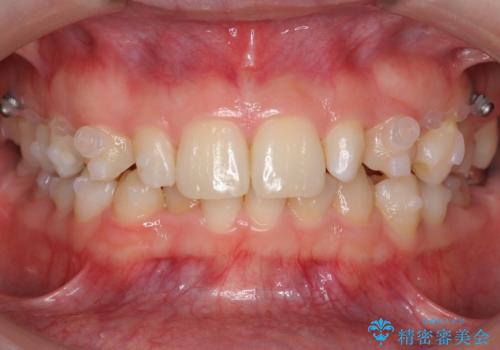

- 前歯を整えたいと来院。

左右の前から2番目の歯が細く、矮小でした。

また、奥歯が2つ並んでおり歯ブラシがしにくい状態でした。